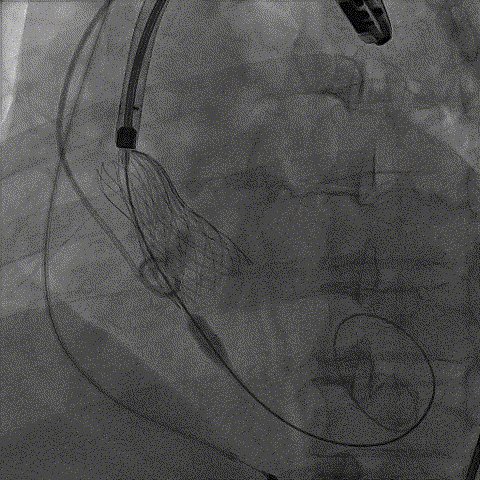

手术影像:

完全释放后造影无漏

外周入路造影良好